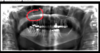

What are these radiographic findings?

Residual Cysts

What is the radiographic finding?

Residual Cyst